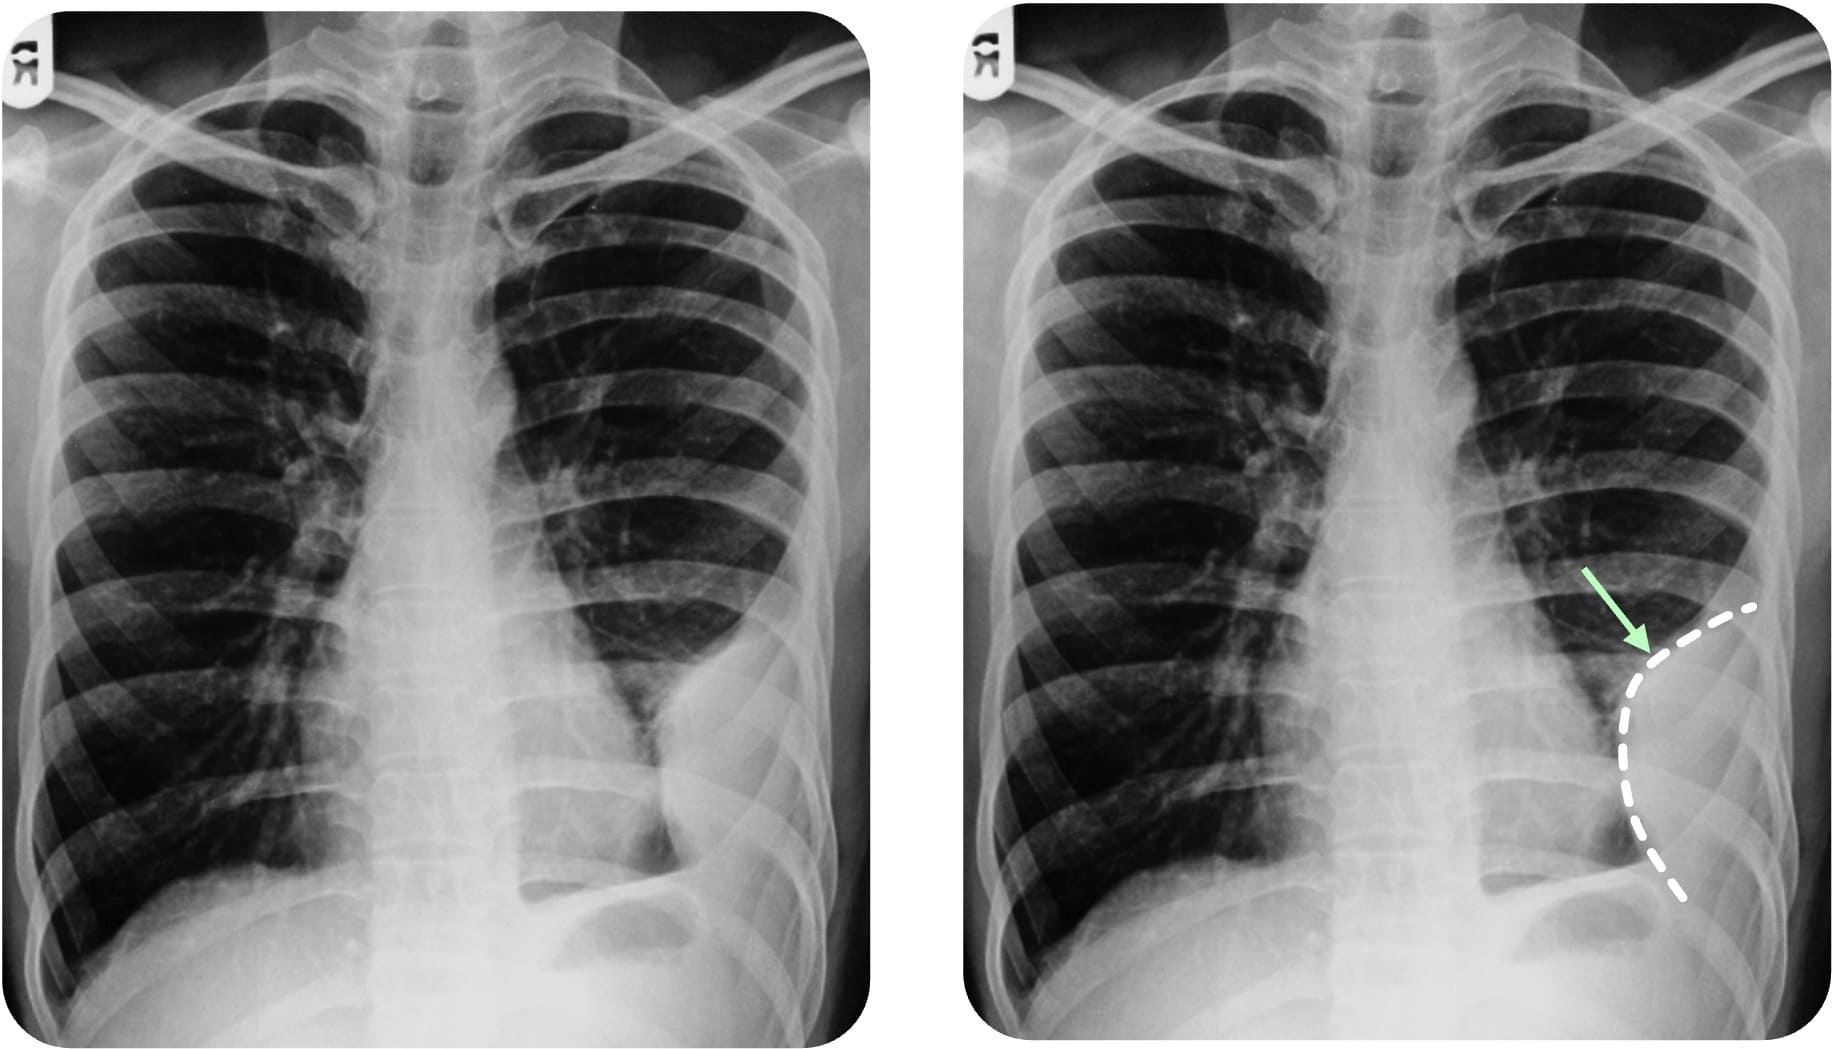

Interlobärerguss

Sonderformen sind der Interlobärerguss, der subpulmonale Erguss und der abgekapselte Erguss. Beim Interlobärerguss befindet sich die Flüssigkeit im Lappenspalt (Fissura obliqua oder horizontalis). Sie ist meist oval begrenzt („Zitronenform“) und insbesondere in der seitlichen Aufnahme gut beurteilbar. Er kann einen Rundherd

Case courtesy of Davison Dzamatira, Radiopaedia.org, rID: 99009

: homogene Transparenzminderung - Interlobarerguss: Pseudotumor